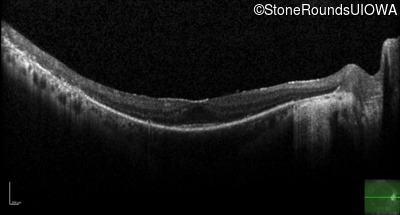

The clinical features supporting the diagnosis of MAK-associated autosomal recessive retinitis pigmentosa in this patient include: night blindness and constricted visual fields (with temporal predilection) as his earliest symptoms; bone-spicule-like pigmentation (with nasal predilection) and narrowed arterioles on fundus examination; loss of outer retinal structures on OCT; a similarly affected sibling; Jewish ethnicity; and, normally sighted parents.

Age at visit: 55 years